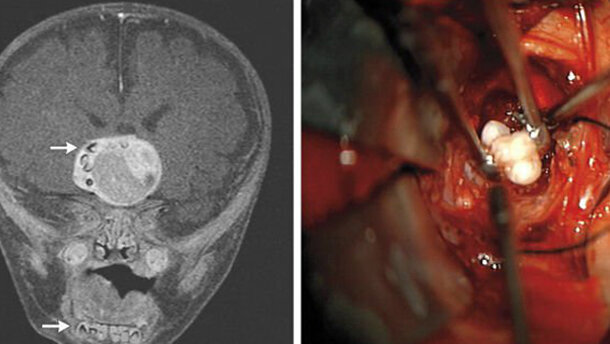

Secondo il rapporto del caso, pubblicato online il 27 febbraio dal New England Journal of Medicine, dopo l’arrivo all’ospedale infantile Johns Hopkins Children’s Center, è stata eseguita una risonanza magnetica al cervello del bambino, che ha rivelato la massa (4,1 cm × 4,0 cm × 3,5 cm) vicino all’ipofisi. I medici hanno inoltre identificato strutture simili ai denti nella mandibola.

Durante la rimozione chirurgica del tumore, i chirurghi hanno trovato un certo numero di denti all'interno della massa, successivamente identificata dall’esame istologico come un Craniofaringioma adamantinomatoso. Tali tumori a evoluzione lenta nascono dalla tasca di Rathke, precursore embrionale dell'ipofisi anteriore, e consistono in residui delle cellule epiteliali squamose e cheratina e componenti cistiche. Le cisti contengono un liquido giallo e viscoso contenente cristalli di colesterolo. I medici hanno spiegato che istologicamente il Craniofaringioma adamantinomatoso assomiglia molto ad alcuni tumori odontogeni.